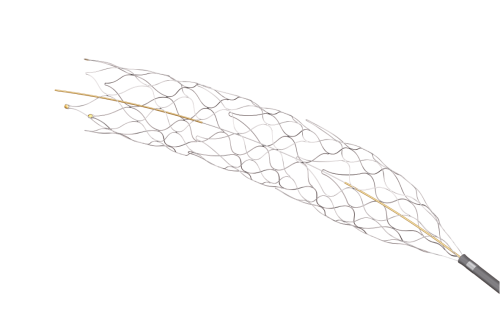

Em Cirurgia Vascular, Endovascular e Radiologia Intervencionista oferecemos uma ampla gama de soluções, incluindo enxertos endovasculares, cateteres de trombectomia e dispositivos de embolização. Esses produtos são vitais para o tratamento de doenças vasculares complexas, como aneurismas e tromboses, proporcionando aos profissionais de saúde as ferramentas necessárias para intervenções precisas e eficazes.